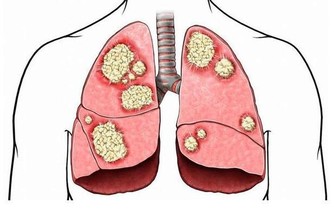

1. 止咳化痰

咳嗽是秋天高發病,一旦得上就很難好,用艾葉泡腳,每天20分鐘,泡第一次就會有改善,並且還能清肺熱,排肺毒。